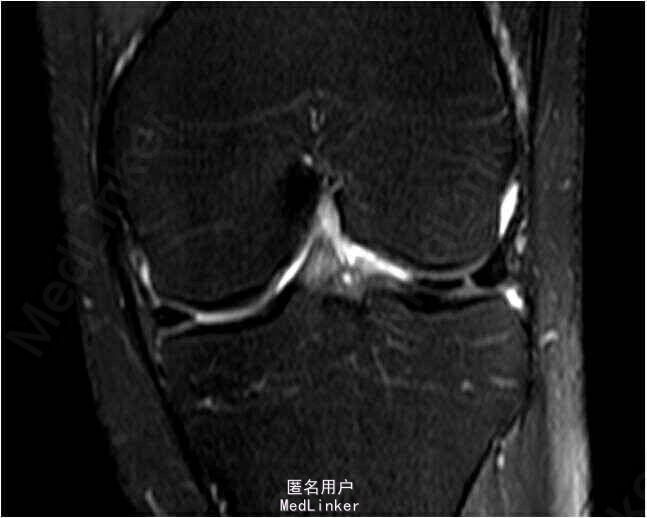

查体:双下肢无畸形,左膝关节关节间隙压痛,麦氏征(+),肢端血运、感觉、活动正常。右下肢及双上肢其余关节未见明显异常。MRI检查提示:左膝关节外侧半月板体部横断裂。

诊断:左膝关节外侧半月板体部横断裂。行手术左膝关节镜检及半月板修补术。术后开始行股四头肌肌力训练及踝泵训练。术后定期门诊复诊并行主被动康复训练。